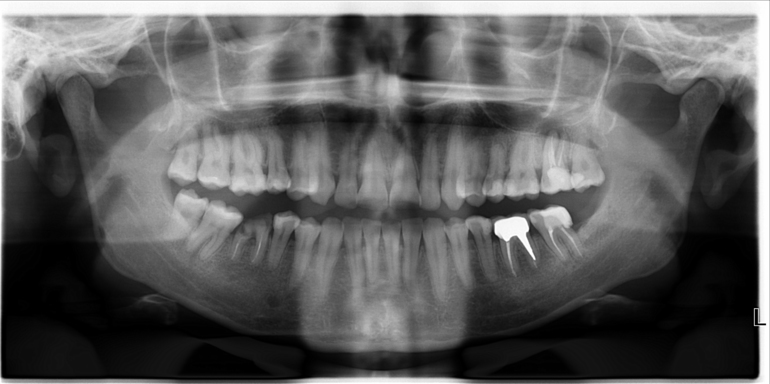

Помогите пожалуйста советом. У меня случилась следующая неприятность с зубом. Два года назад удалили из него нерв. С тех пор ничего не беспокоило. И вот недавно стоматолог на снимке увидела воспаление около корня этого зуба, сказала, что зуб нужно удалять. Сначала я не поверила (было очень неожиданно это услышать), обратилась к другим врачам, дополнительно сделала КТ. И все доктора , кто видел мои снимки (порядка 7 человек), сошлись во мнении, что зуб необходимо удалить(((.

Причина же возникшего воспаления в «некачественном лечении». Как показало КТ, у моего зуба один канал не до конца запломбирован, повреждена его боковая стенка. При этом, как правило, на мой прямой вопрос: «Виновата ли доктор, которая удаляла нерв из зуба?» врачи, с которыми я консультировалась, прямого ответа не дают. Может быть, тут врачебная солидарность работает, а может быть, и действительно все возможное было сделано, просто качество рентгена и доступ к этому зубу не позволили хорошо проконтролировать запломбирован ли канал до конца.